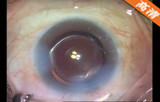

该手术透明角膜切口,注入粘弹剂 ,辅助切口;,连续环形撕囊;水分离、水分层; 超声乳化吸除晶状体核 ,灌注抽吸手柄(I/A)抽吸出残留的晶状体皮质; 后囊膜抛光 ,注入粘弹剂 。植入折叠人工晶体, 吸除医用透明质酸钠凝胶 ,水密切口 。